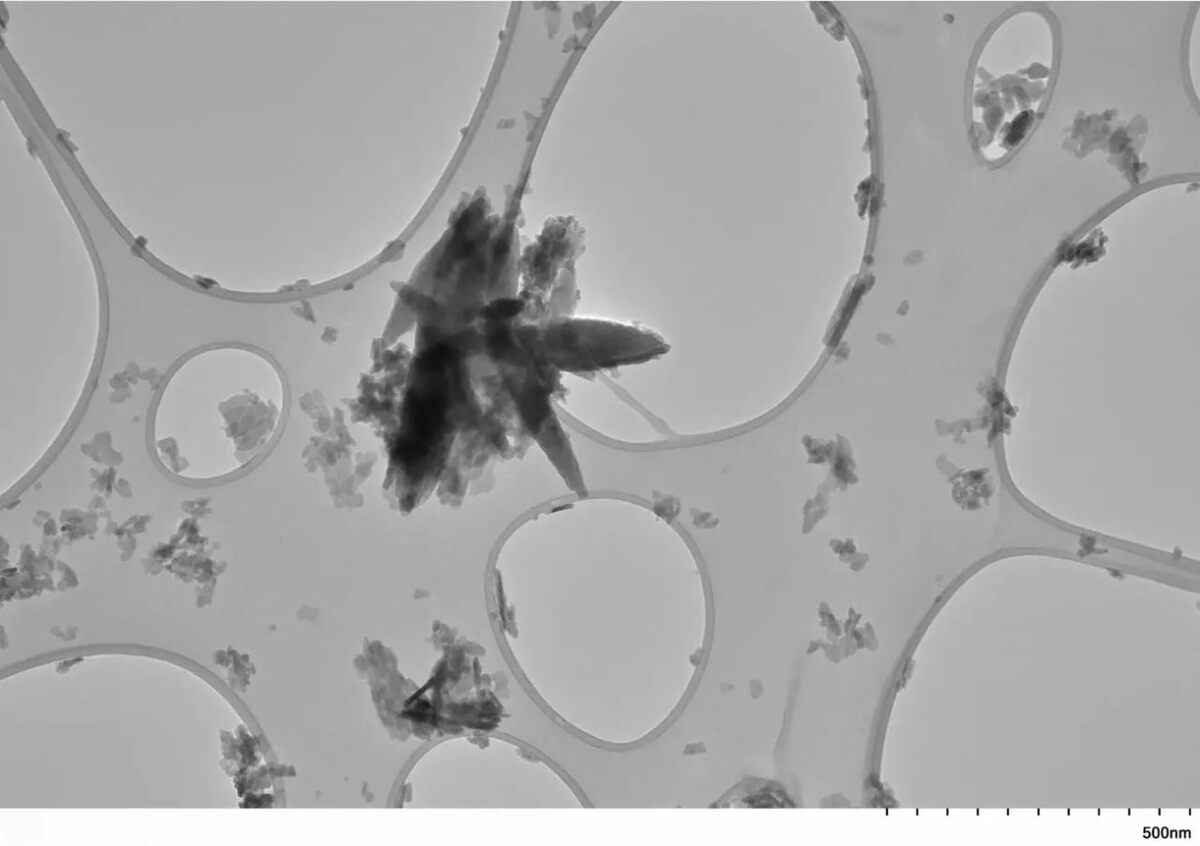

На фото: нанопластические осколки из сгустков в сонной артерии. Исследование представлено 22  апреля 2025 г., на сессии Американской кардиологической ассоциации в  Балтиморе; рецензируемая публикация ожидается к  концу года.

Учёные из  Университета Нью‑Мексико нашли в 51 раз больше микропластика и  нанопластика в бляшках сонных артерий пациентов, переживших инсульт или потерю зрения, чем в здоровых артериях. Пластик не просто лежит “балластом” — клетки с его высоким содержанием демонстрируют изменённую генную активность, связанную с  воспалением и  стабильностью бляшек.